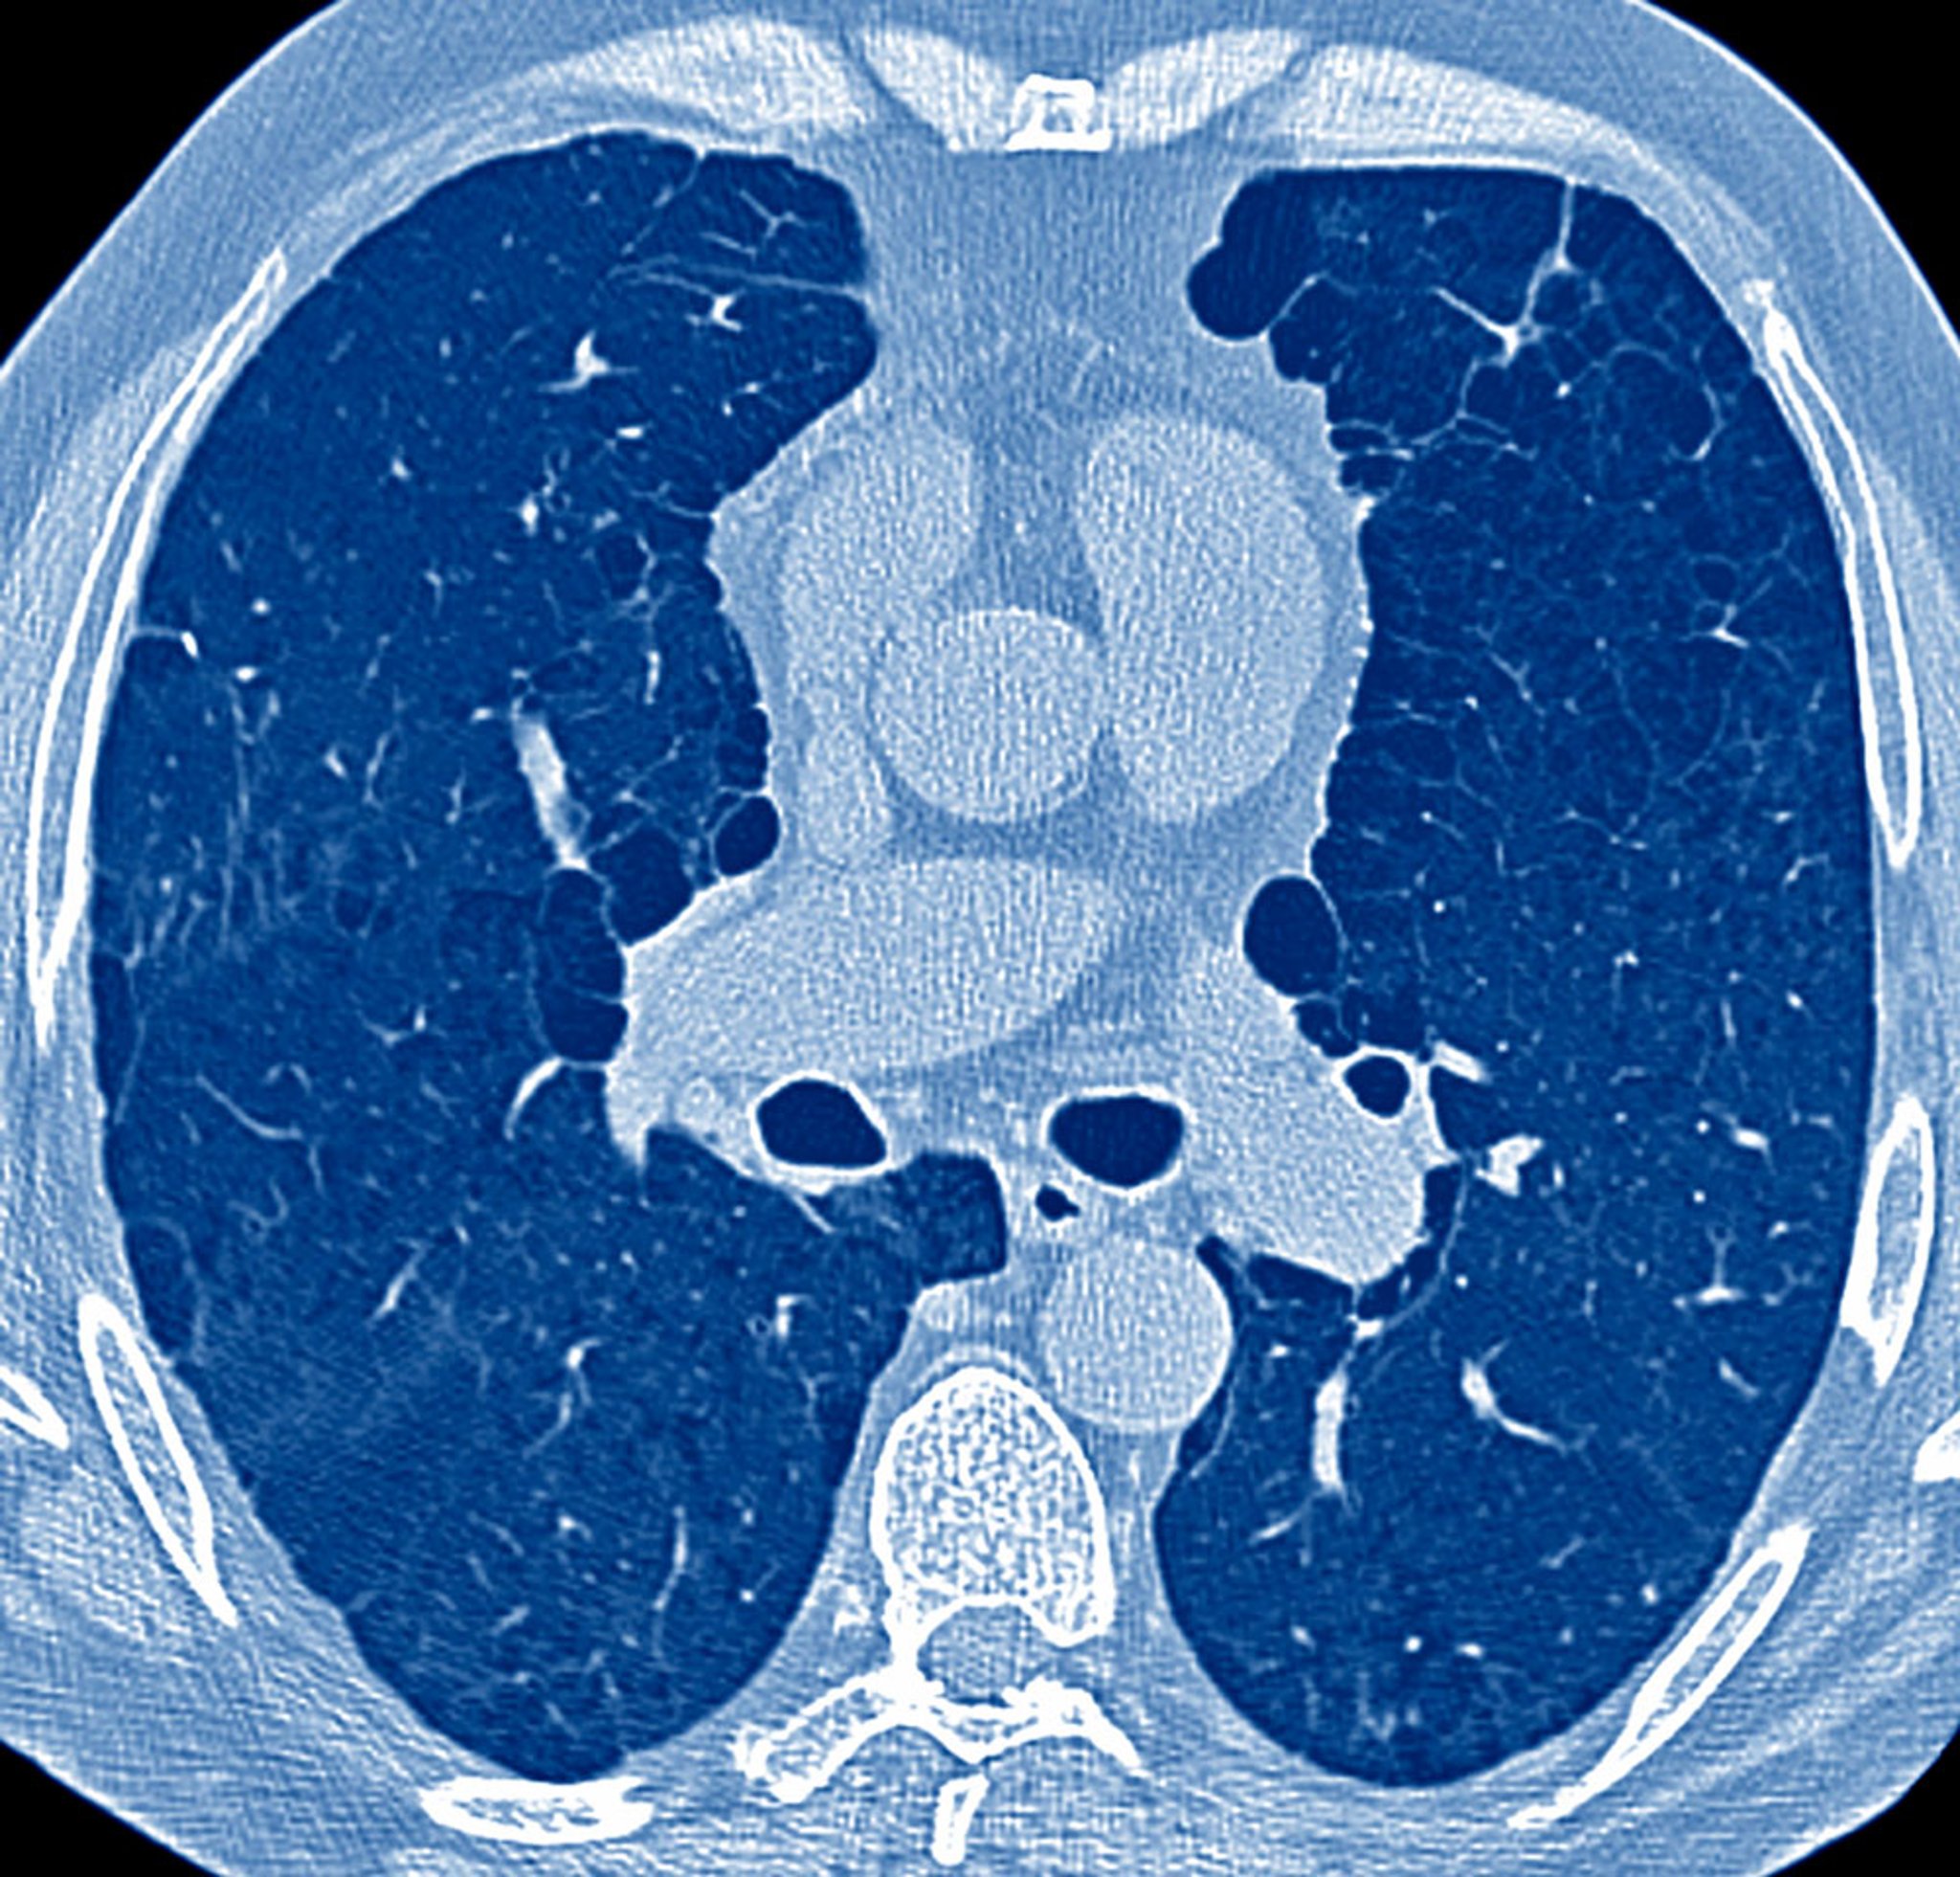

肺气肿患者前后径增大

这张CT图像显示吸烟患者肺气肿改变,前后径显著增大。体格检查时会发现桶状胸。